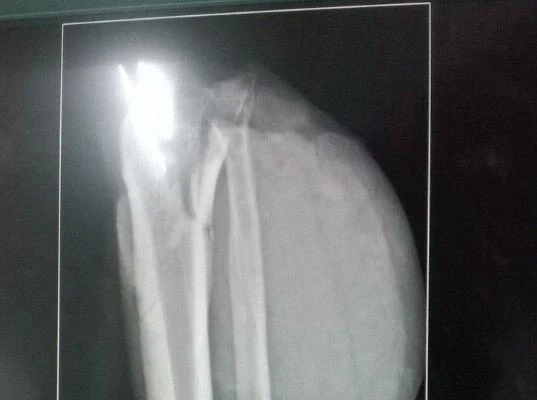

Kết quả chụp X quang ghi nhận đùi chân trái ông D bị đứt lìa.

Kết quả chụp X quang ghi nhận đùi chân trái ông D bị đứt lìa. Ảnh: HÒA KHÁNH